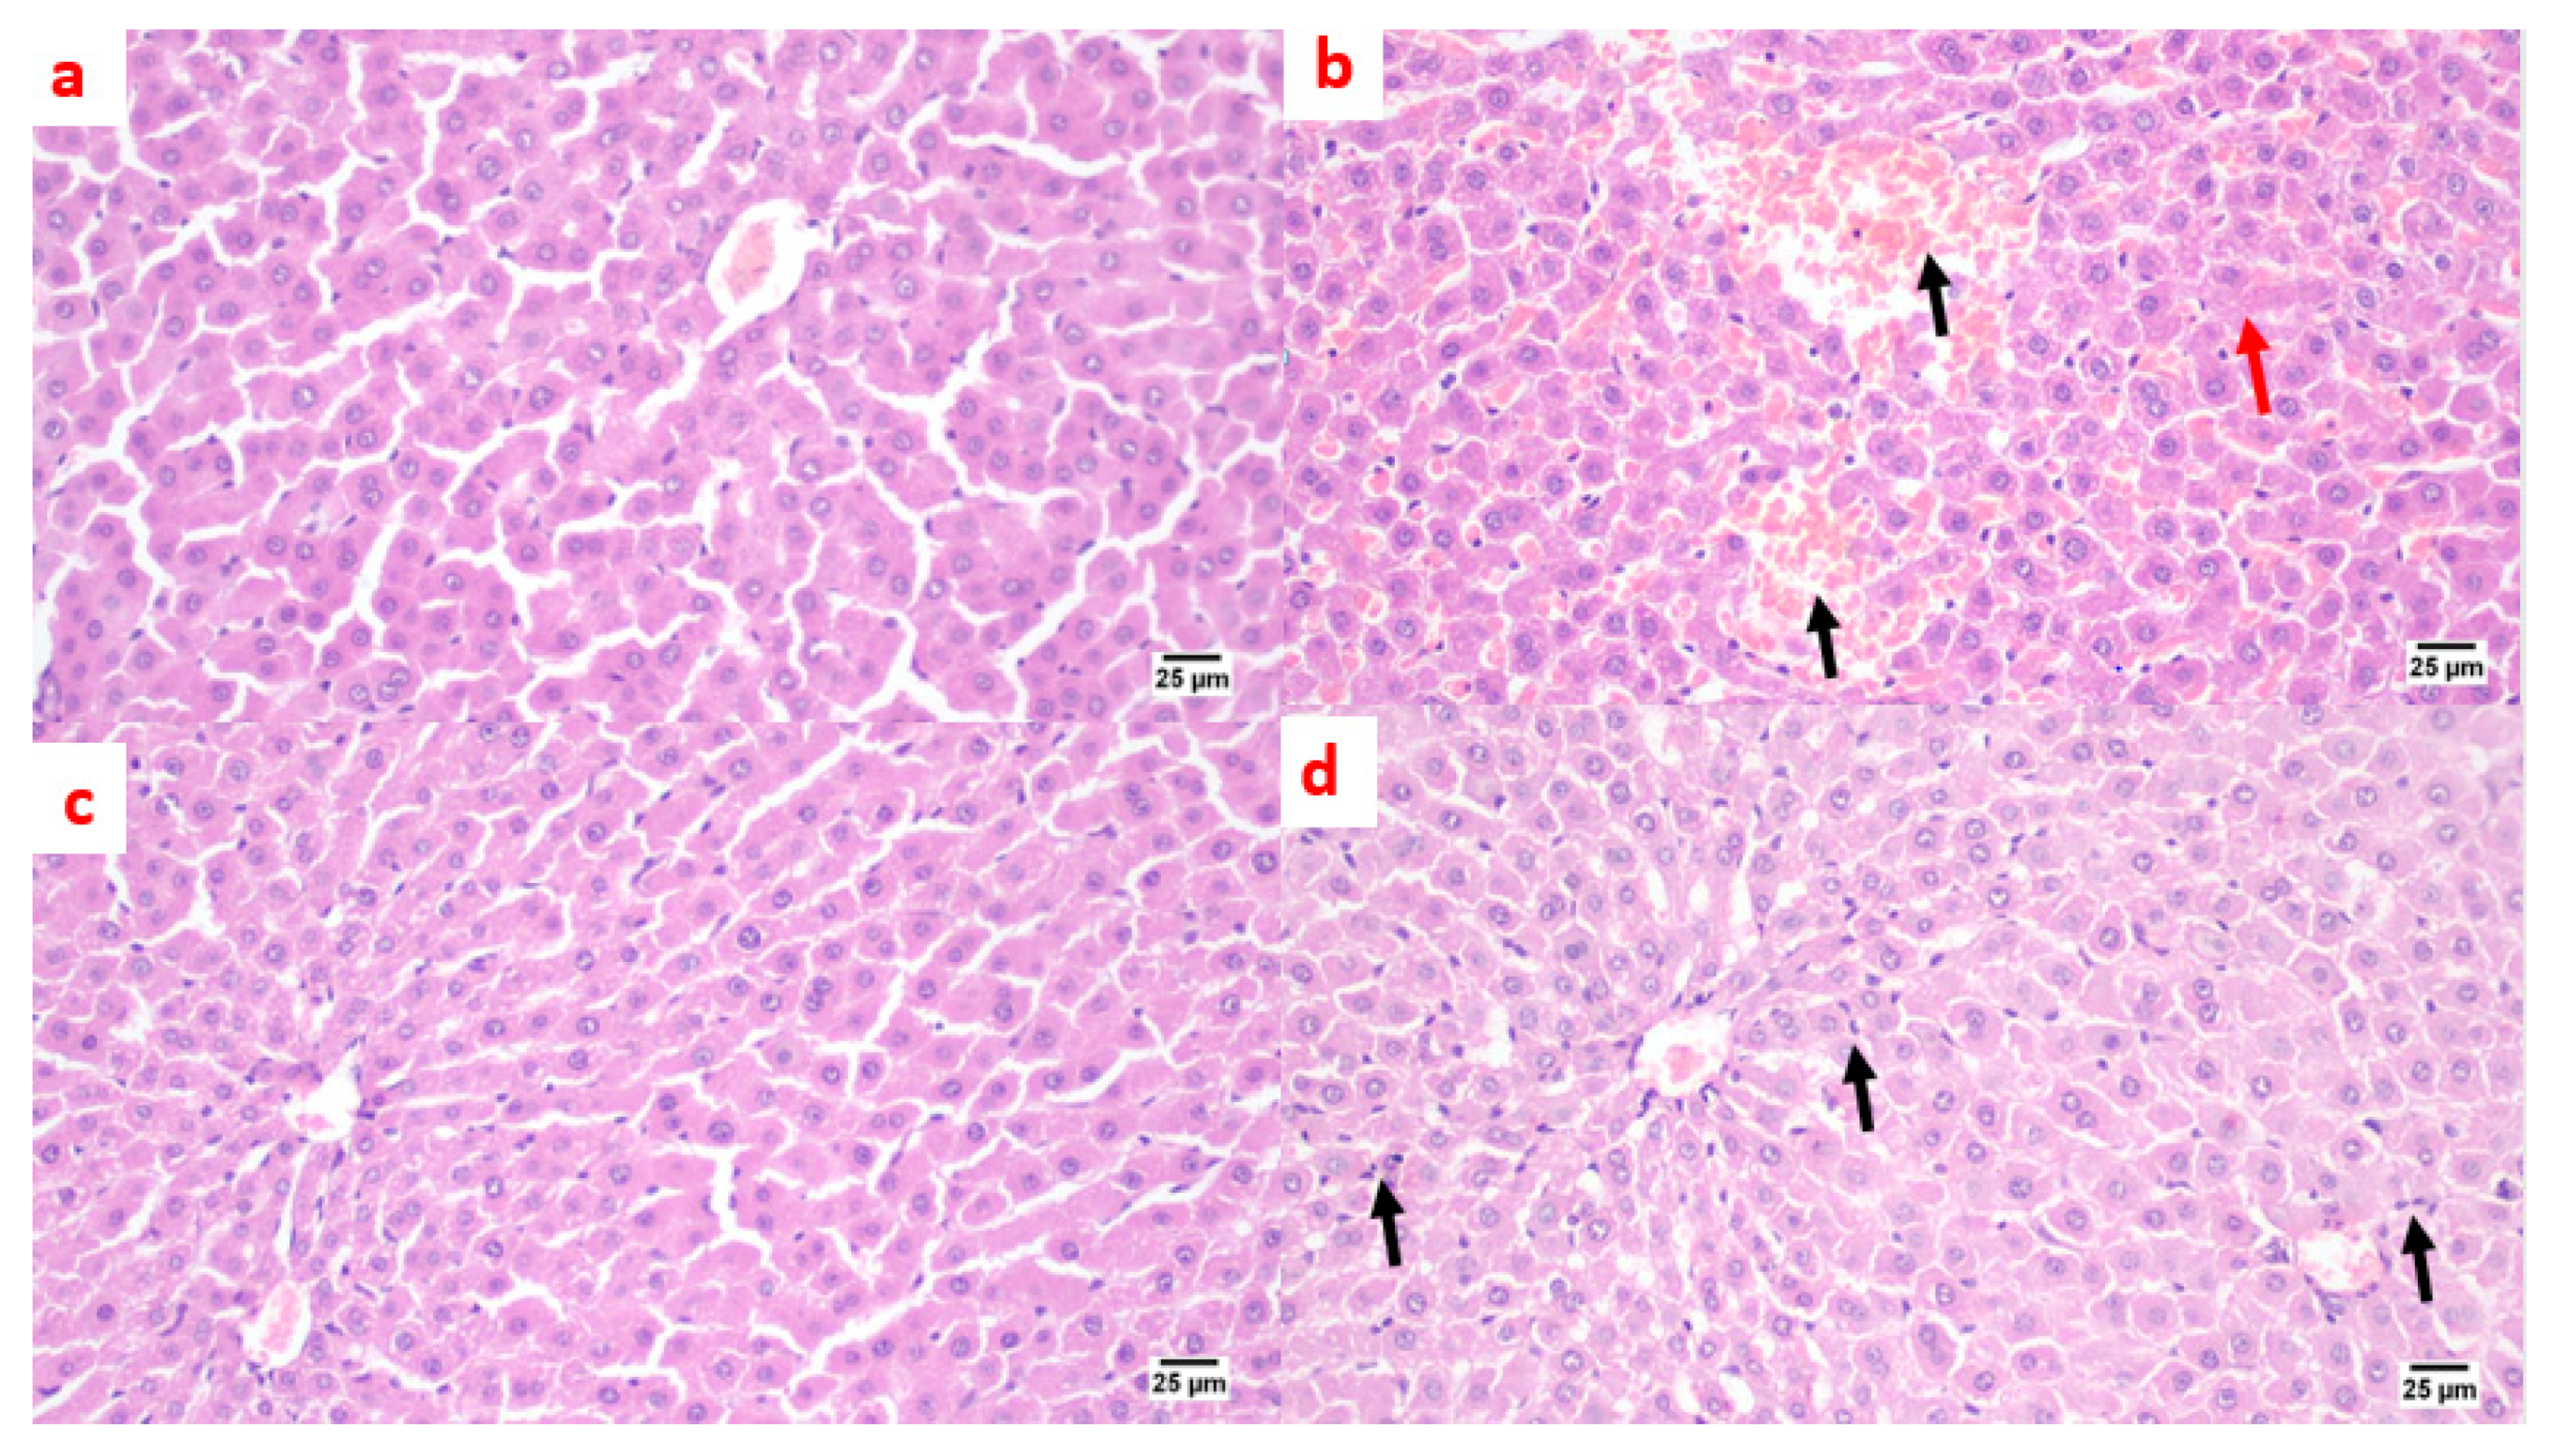

A microscopic examination of liver tissue showed a normal histology. The hepatocytes were arranged in parallel cords radiating from the central vein toward the portal area that contained branches of the portal vein, hepatic artery, and bile duct (Figure 7a). On the contrary, in the positive control group, liver tissue exhibited some histopathological alterations; the portal areas were mildly expanded by mild fibroplasia and mononuclear inflammatory cell infiltration. The bile ducts within the portal areas were hyperplastic, and the portal blood vessels were severely congested. Focal areas of parenchymal loss were observed with hemorrhages and marked sinusoidal dilatation. Moreover, some hepatocytes suffered sporadic cell necrosis (Figure 7b). Regarding the treatment with pioglitazone, the hepatic parenchyma was normal, without any detectable histopathological alterations (Figure 7c). The livers of the benzenesulfonamide-derivative-treated synthetic group showed apparently normal hepatic parenchyma in almost all examined sections. Few sections showed mild hyperplasia in the Kupffer cells, with mononuclear inflammatory cells infiltration at the portal area. (Figure 7d).

Photomicrographs of rat liver sections stained with H&E showing the effect of 14 days of oral administration of pioglitazone and the synthetic compound against STZ-induced type 2 DM. (a) Normal control section (25 µm). It appears normal histologically. The hepatocytes were arranged in parallel cords radiating from the central vein toward the portal area that contained branches of the portal vein, hepatic artery, and bile duct. On the contrary, (b) the positive control group section (25 µm) shows mononuclear inflammatory cell infiltration at the portal area with a hemorrhage (black arrow), a hyperplastic bile duct, sinusoidal dilatation, and a few necrotic hepatocytes (red arrow). (c) The pioglitazone-treated section (25 µm) shows the hepatic parenchyma was normal, without any detectable histopathological alterations. (d) The synthetic compound section (25 µm) shows a normal hepatic parenchyma with mild hyperplasia in the Kupffer cells, with mononuclear inflammatory cells infiltration at the portal area (black arrows).

Lantheir et al. [29], demonstrated that selective ablation of Kupffer cells significantly increases high-fat diet-induced hepatic insulin resistance. This confirms its important pathological role in the initiation of insulin resistance. Besides, the inflammatory changes occurring in the adipose tissue, which is responsible for the release of prostaglandin E2 that is involved in the modulation of hepatic glucose output, regulation of cytokine production, and induction of insulin resistance in hepatocytes in collaboration of IL-6, induced a significant increase in Kupffer cells and the pro-inflammatory activation of Kupffer cells [30]. Moreover, an ischemia/reperfusion exposed liver model showed apparent broad hemorrhagic necrosis, extensive areas of portal inflammation, and a moderate increase in inflammatory cell infiltration, and this histological damage was ameliorated by losartan [31]. In addition, a diabetic rat model treated with losartan showed a decrease in the number of inflammatory cells at the liver tissue [32]. These data couple with our histopathological liver data that are shown in Figure 7.